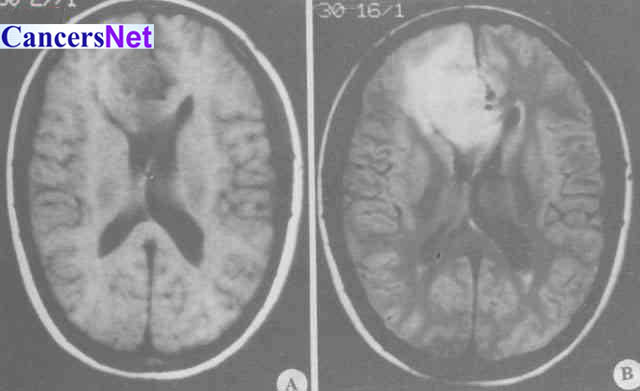

胶质母细胞瘤